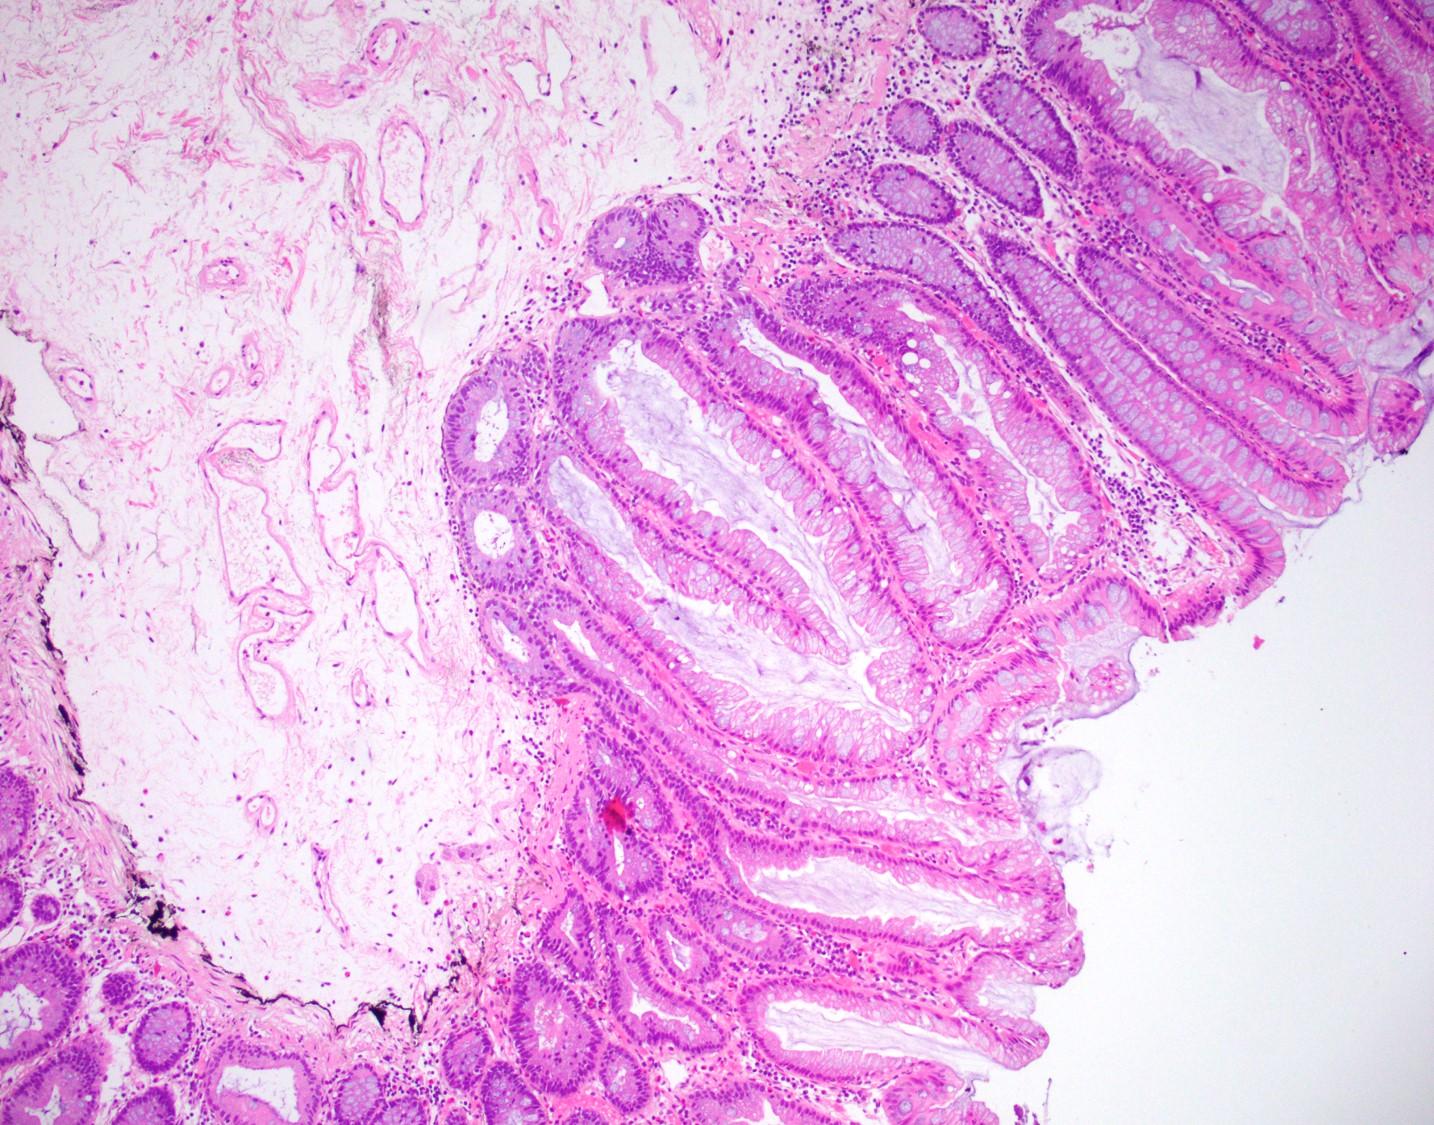

67 yo M w/ multiple, morphologically similar polyps in colon (click the photos below to enlarge).

C. Serrated polyposis syndrome

Serrated polyp is an umbrella term that includes any of the following:

- Hyperplastic polyps

- Sessile serrated polyps/adenomas

- Traditional serrated adenomas